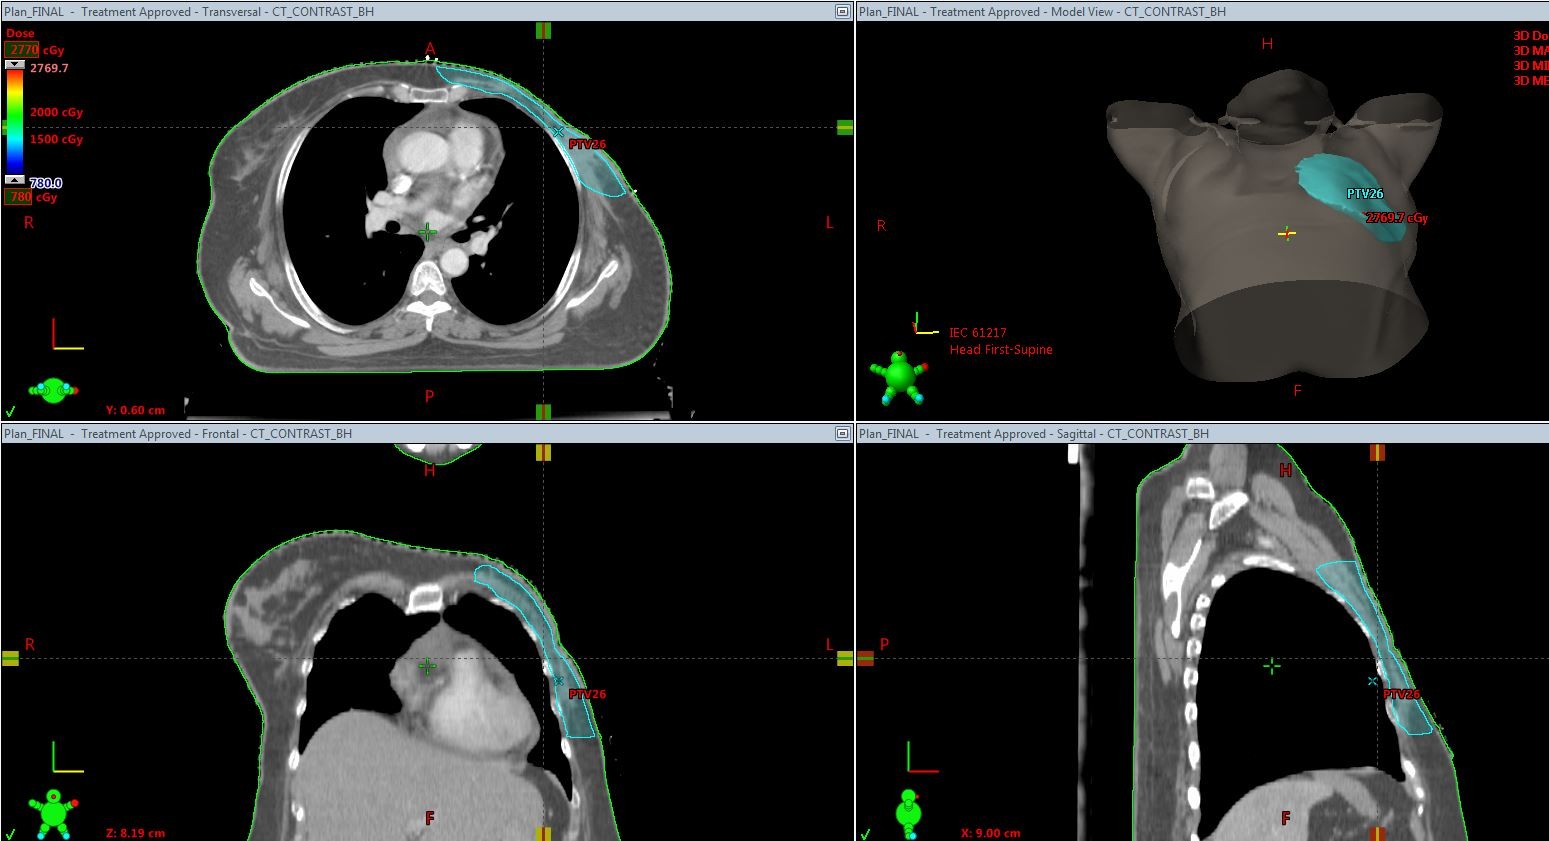

Plan evaluation

Multiple plans were made for each patient ensuring maximum  dose coverage to the planning target volume,minimizing dose to heart and lung according to the fast forward protocol.The ideal dose coverage for 95% of the target volume is 95% of the dose. The best plan was selected by the radiation oncologist and was executed (Picture 4).

Picture 4-95% dose distribution curve

The following criteria for dose coverage were given as per the fast forward planning pack protocol to get the optimum results.(Table-2).The final decision is taken by the oncologist prioritising normal tissue dose constraints  over the target coverage constraints. Medical physicists aimed at reducing the amount of lung and heart in the treated area by  MLC shielding on the tangential fields and also by shifting the field borders according to the particular case without compromising the position of the area of interest.(8)